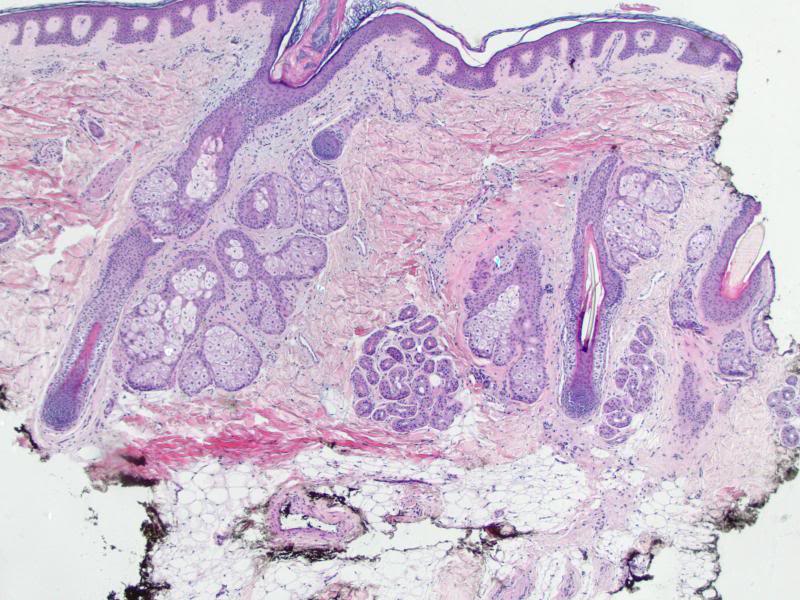

Hair transplant strip showing marked perifollicular fibrosis

Evaluation of perifollicular inflammation of donor area during hair transplantation in androgenetic alopecia and its comparison with controls

Background: Mild perifollicular inflammation is seen in both androgenetic alopecia (Androgenetic Alopecia) cases and normal controls, whereas moderate or dense inflammation with concentric layers of collagen, is seen in Androgenetic Alopecia cases but only in very few normal controls, and may lessen the response to topical minoxidil. Moderate or dense lymphocytic inflammation and perifollicular fibrosis have poor hair growth following transplantation. Aim: The purpose of the study is to evaluate the perifollicular lymphocytic inflammation and fibrosis in Androgenetic Alopecia patients during follicular unit hair transplantation (FUT) and its comparison in normal controls. Materials and Methods: A total of 21 male patients with Androgenetic Alopecia and 7 matched controls participated in the study. Histopathological analysis of biopsy specimens from donor strip of patients during the hair transplantation and two 4 mm punch biopsies on controls were performed. Morphometric analysis was performed and perifollicular fibrosis was scored based on the width of the condensed collagen at the lower infundibulum and isthmus from 0 to 3. Perifollicular infiltrate was also scored 0-3 and a total score of 3 or more out of 6 was considered significant. Results: Nearly 76% of Androgenetic Alopecia patients had perifollicular fibrosis more than 50 μm at ×200 magnification. Almost 33.33% patients had moderate/dense perifollicular lymphocytic infiltrate whereas none of the controls had it. Total score in Androgenetic Alopecia cases was significantly higher than controls (P = 0.012) using Chi-square test. Out of 21 patients, 13 had a score of 3 or more and were followed-up with monthly treatment with intralesional steroids using a dermaroller. Conclusion: Histopathological evaluation of the donor area is a must during hair transplantation to evaluate the extent of perifollicular inflammation and achieve better results by following it up with treatment directed to decrease the inflammation.

Scalp pathology in androgenetic alopecia: horizontal section. Severe peri-isthmus and peri-sebaceous lymphocytic infiltrates with perifollicular fibrosis (HE ×60)

Scalp pathology in androgenetic alopecia: vertical section. Mild perifollicular fibrosis in the dermis (HE ×70)